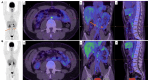

Figures